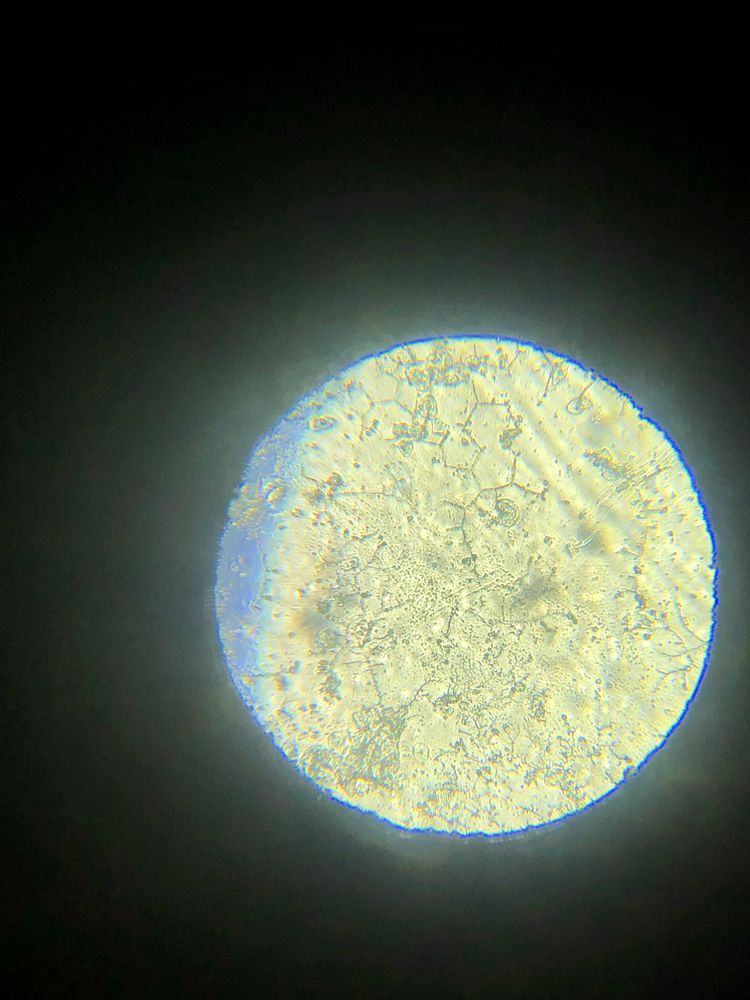

Я читала, что тесты на о показывают б. Возможно ли что и микроскоп на о, показал б.

Я уже ловила о в этом цикле, а по бт поймала из, ну как я думала, как тут вдруг. Вторая о или это первый признак б. Давайте попробуем разобраться. Подобного я р